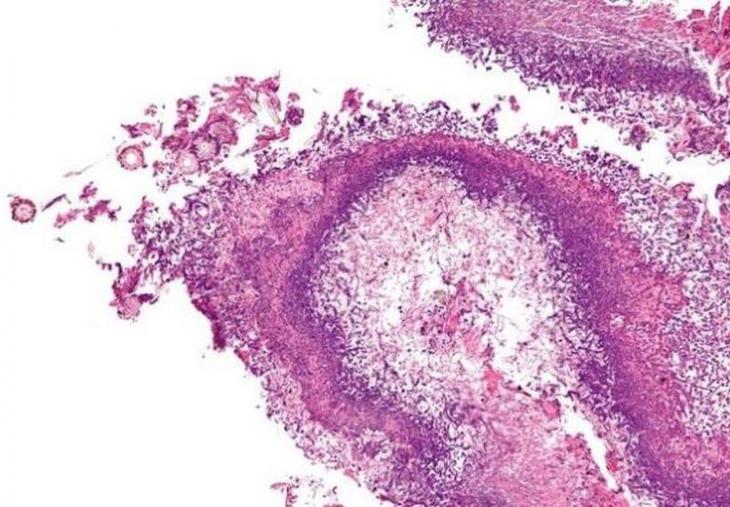

10. Mycobacterium tuberculosis, или палочка Коха

Бактерия, вызывающая туберкулез. Смертность чрезвычайно высока даже в наши дни: это заболевание входит в десятку ведущих причин человеческой гибели. Примерно четверть населения планеты имеет латентный туберкулез. Это значит, что заболевание может проявить себя в любой момент, стоит иммунитету лишь «дать слабину». В России туберкулез уносит около 20 000 жизней ежегодно. Главная причина такого размаха в том, что палочка Коха легко передается воздушно-капельным путем. Для профилактики туберкулеза врачи советуют проходить флюорографическое обследование не реже одного раза в год.